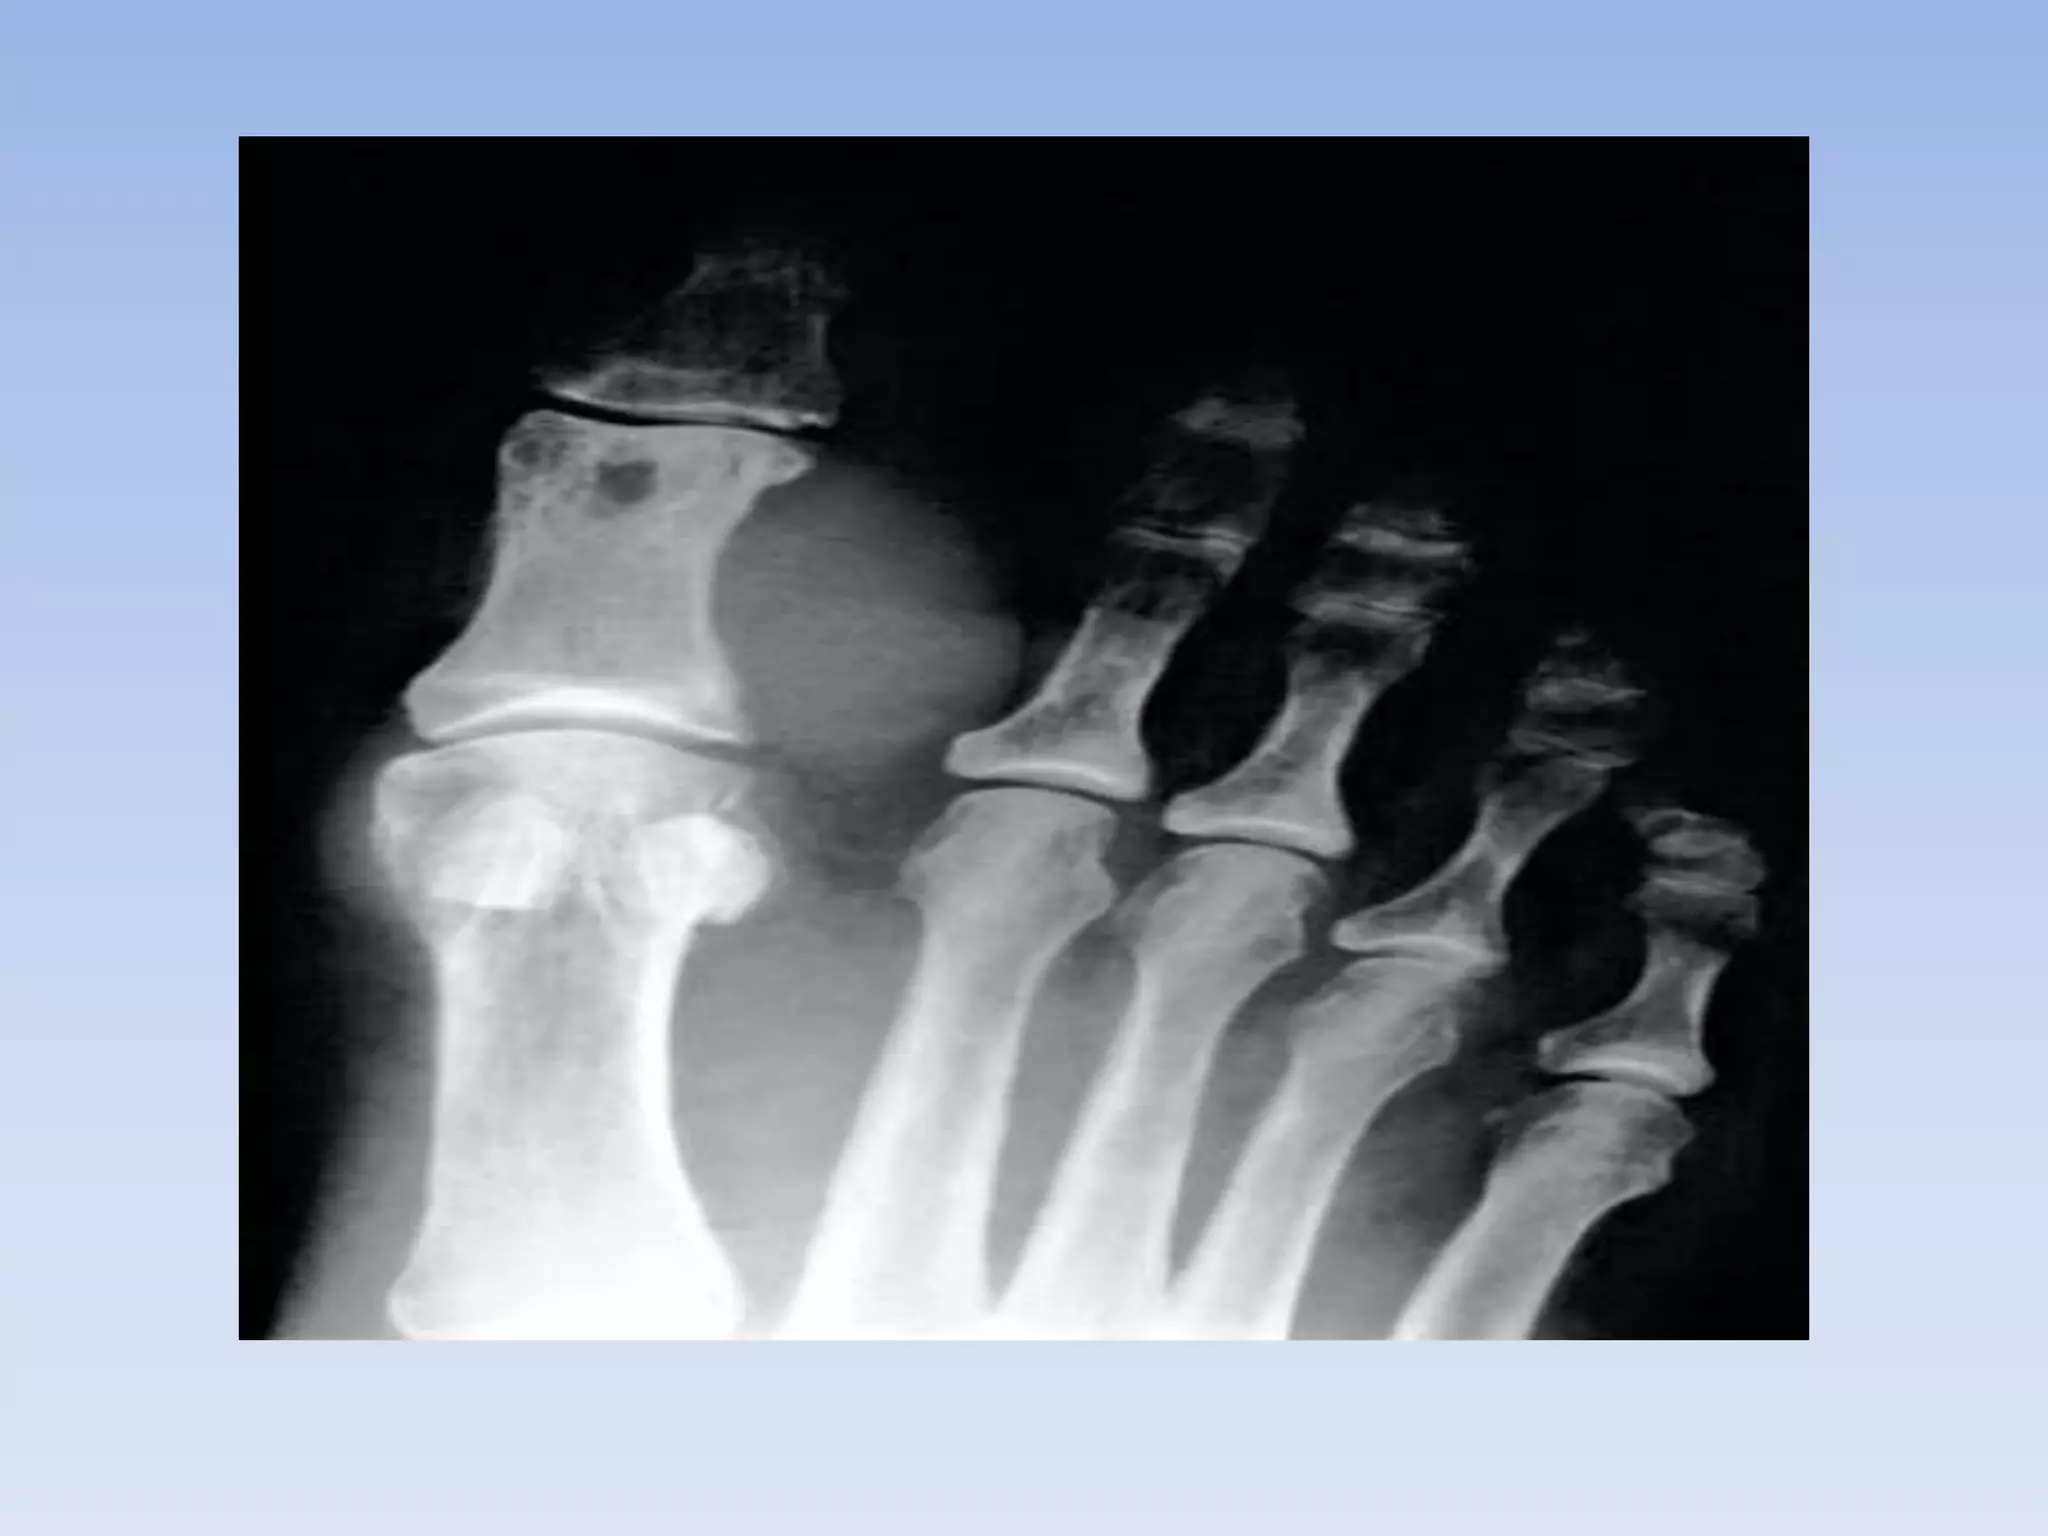

• The diffuse form typically

involves the large joints , while

the localized form typically

occurs around the small joints

of the hands and fee

• The diffuseform typically involves the large joints , while the localized form typically occurs around the small joints of the hands and fee